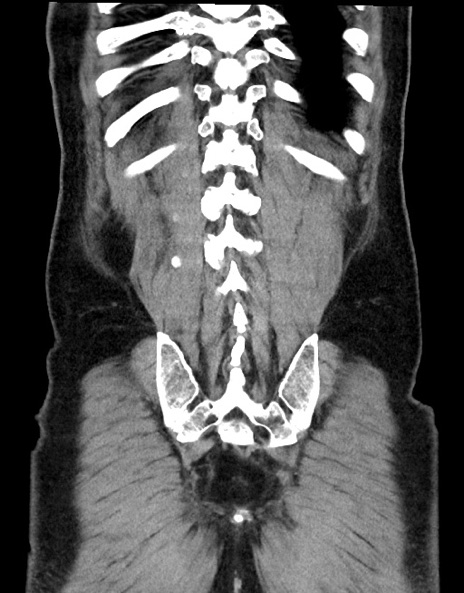

症例15(冠状断像)

【症例】70歳代男性

【主訴】腹痛

【現病歴】今朝から腹痛あり。全体的に痛い。特に左上の方。排ガスが今日はない。冷や汗が出る。

【既往歴】直腸癌術後

【身体所見】左側腹部〜上腹部に圧痛あり。腹膜刺激症状明らかなではない。軽度反跳痛。左下腹部に術後瘢痕あり。

【データ】WBC 7700、CRP 0.02